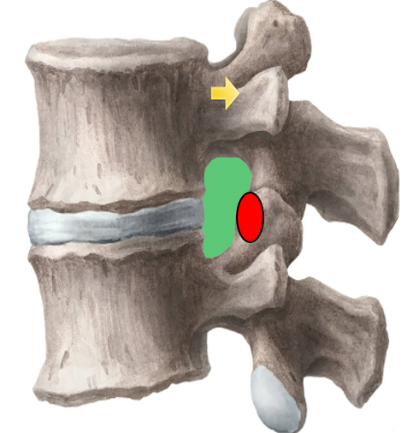

为解决以上问题���,我们提出“椎间孔镜按需成型5级法”��,即将椎间孔镜术中椎间孔成型的实际操作范围进行分级���:0级����:不成型����,见图 1��;1级���:软组织成型�����,只去除关节囊等部分软组织�����,基本不做骨性成型���,见图 2���;2级�����:少许骨质成型���,但不显露下关节突关节面����,见图 3����。3级成型�����:上关节突尖部或上1/2去除成型���,显露下关节突关节面���,见图 4�����;4级成型����:上关节突大部分成型或伴有部分椎弓����、峡部或下关节突小部分���,但预留基底部一部分��,见图 5��。

2���、建立五级成型的有限元模型

正常腰椎模型命名为M0���;0级成型为M1��:不做骨性成型���;1级成型为M2���:软组织成型����,只去除关节囊等部分软组织���,基本不做骨性成型��;2级成型为M3����:少许骨质成型��,不显露下关节突关节面����;3级成型为M4a与M4b���:上关节突尖部(M4a)或上1/2(M4b)去除成型���,显露下关节突关节面����;4级成型为M5�����:上关节突大部分成型或伴有部分椎弓���、峡部或下关节突小部分�����,但预留基底部一部分���,见图16-20���。每组模型都按照前屈����、后伸���、左屈����、右屈���、左旋及右旋6种状态加载��,其他约束条件不变���,观察各组成型对于腰椎活动度及椎间盘应力的影响���。